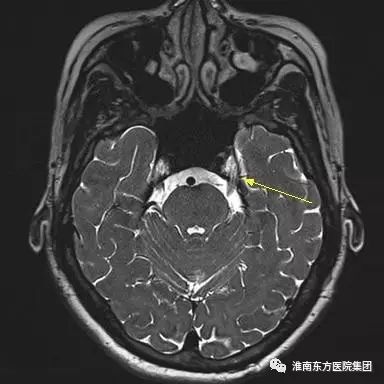

三叉神经